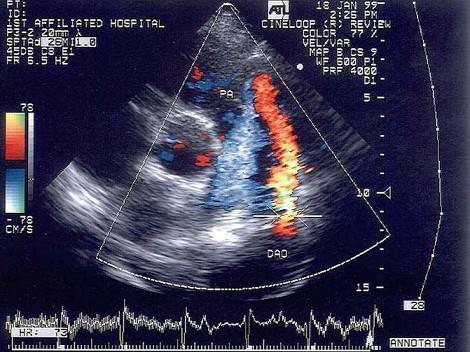

该病例最有可能诊断?(?)A.肺动脉内径增宽B.动脉导管未闭C.肺动脉瓣狭窄D.肺动脉瓣关闭不全E.右室流出道狭窄

选项 A.肺动脉内径增宽 B.动脉导管未闭 C.肺动脉瓣狭窄 D.肺动脉瓣关闭不全 E.右室流出道狭窄

答案 B